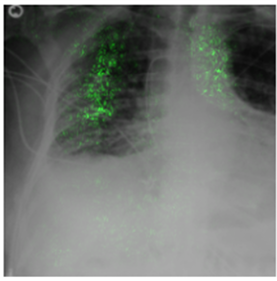

Deep Learning of neural networks has progressively become more prominent in healthcare with models reaching, or even surpassing, expert accuracy levels. However, these success stories are tainted by concerning reports on the lack of model transparency and bias against some medical conditions or patients' sub-groups. Explainable methods are considered the gateway to alleviate many of these concerns. In this study we demonstrate that the generated explanations are volatile to changes in model training that are perpendicular to the classification task and model structure. This raises further questions about trust in deep learning models for healthcare. Mainly, whether the models capture underlying causal links in the data or just rely on spurious correlations that are made visible via explanation methods. We demonstrate that the output of explainability methods on deep neural networks can vary significantly by changes of hyper-parameters, such as the random seed or how the training set is shuffled. We introduce a measure of explanation consistency which we use to highlight the identified problems on the MIMIC-CXR dataset. We find explanations of identical models but with different training setups have a low consistency: $\approx$ 33% on average. On the contrary, kernel methods are robust against any orthogonal changes, with explanation consistency at 94%. We conclude that current trends in model explanation are not sufficient to mitigate the risks of deploying models in real life healthcare applications.